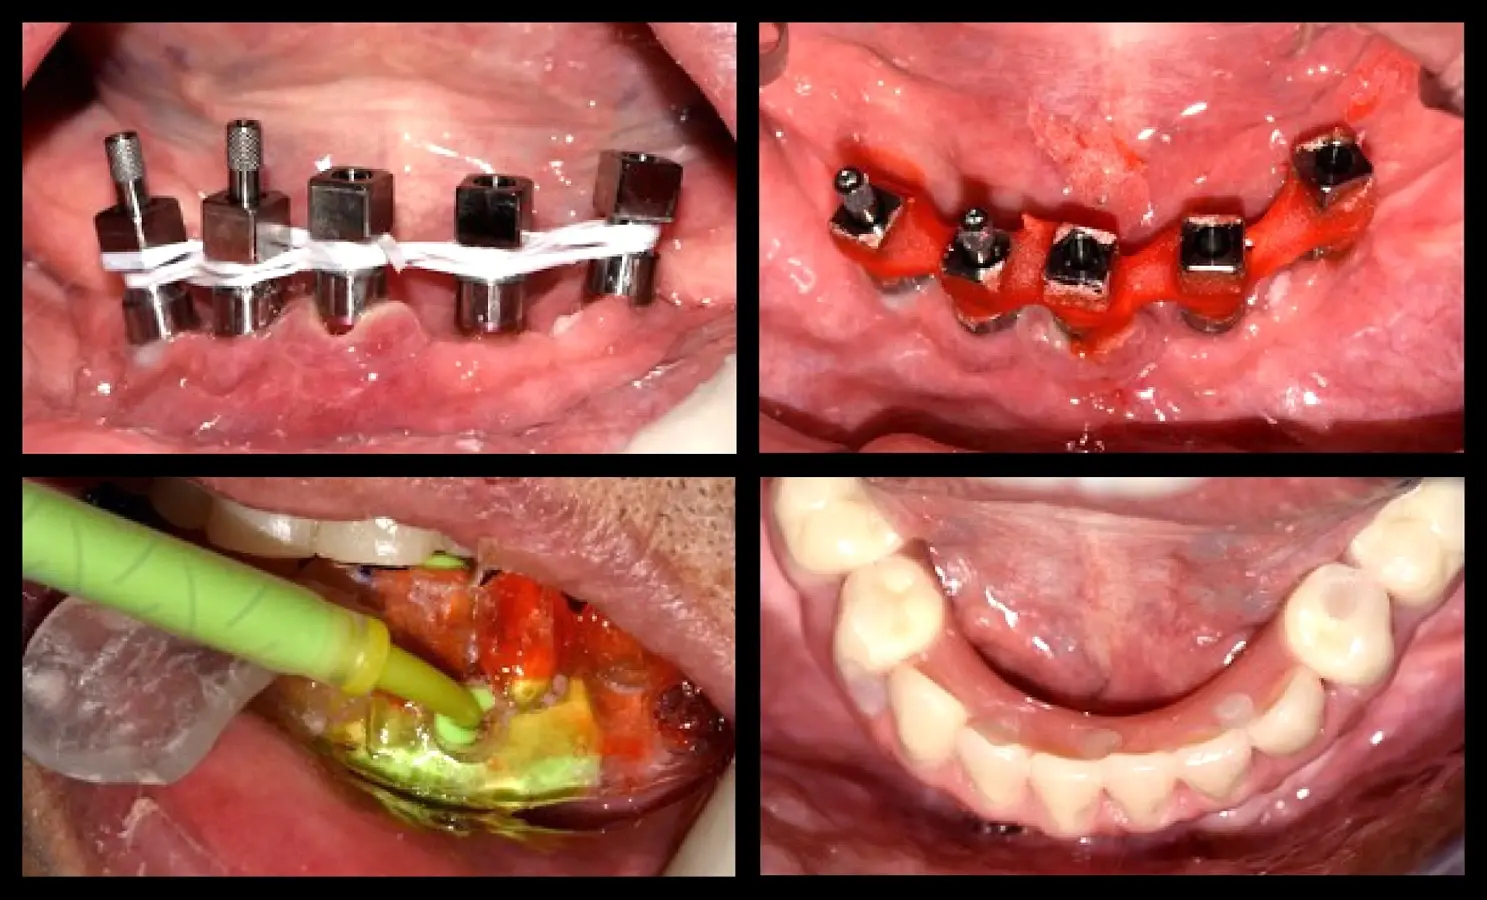

La segunda fase quirúrgica y colocación de pilares intermedios fue realizada en la semana 18, siguiendo la recomendación del fabricante con un torque de 20 Ncm. Se realizó la impresión del maxilar superior y la transferencia de los implantes del maxilar inferior. Una vez corroborado el asentamiento de ambas estructuras en boca se envió al laboratorio para el enfilado de la estructura inferior. Finalizada la prótesis fue instalada en el paciente (Figura 10).